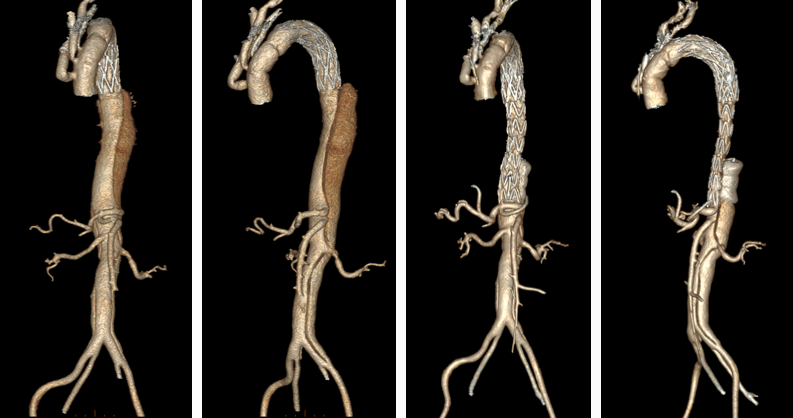

★ WeFlow-EndoPatch腔内补片系统

1.手术步骤:

15例患者完成术后6个月CTA影像学随访。15例患者术前胸主动脉假腔最大直径 33.61±26.95 mm,术后6个月胸主动脉假腔最大直径缩小为 28.92±24.22 mm;术前腹主动脉假腔最大直径 25.96±7.27 mm,术后6个月腹主动脉假腔最大直径缩小为 22.07±5.69 mm。

*15例患者共植入29枚补片

15例患者术后6个月胸降主动脉段及腹主动脉段假腔均实现血栓化。